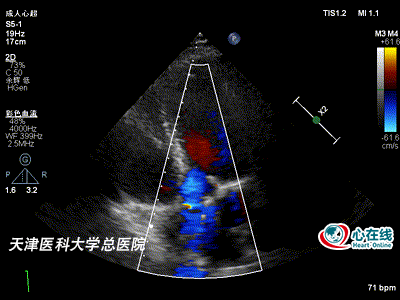

彩色多普勒心尖五腔心切面示人工主动脉瓣前向血流速度增快,呈五彩